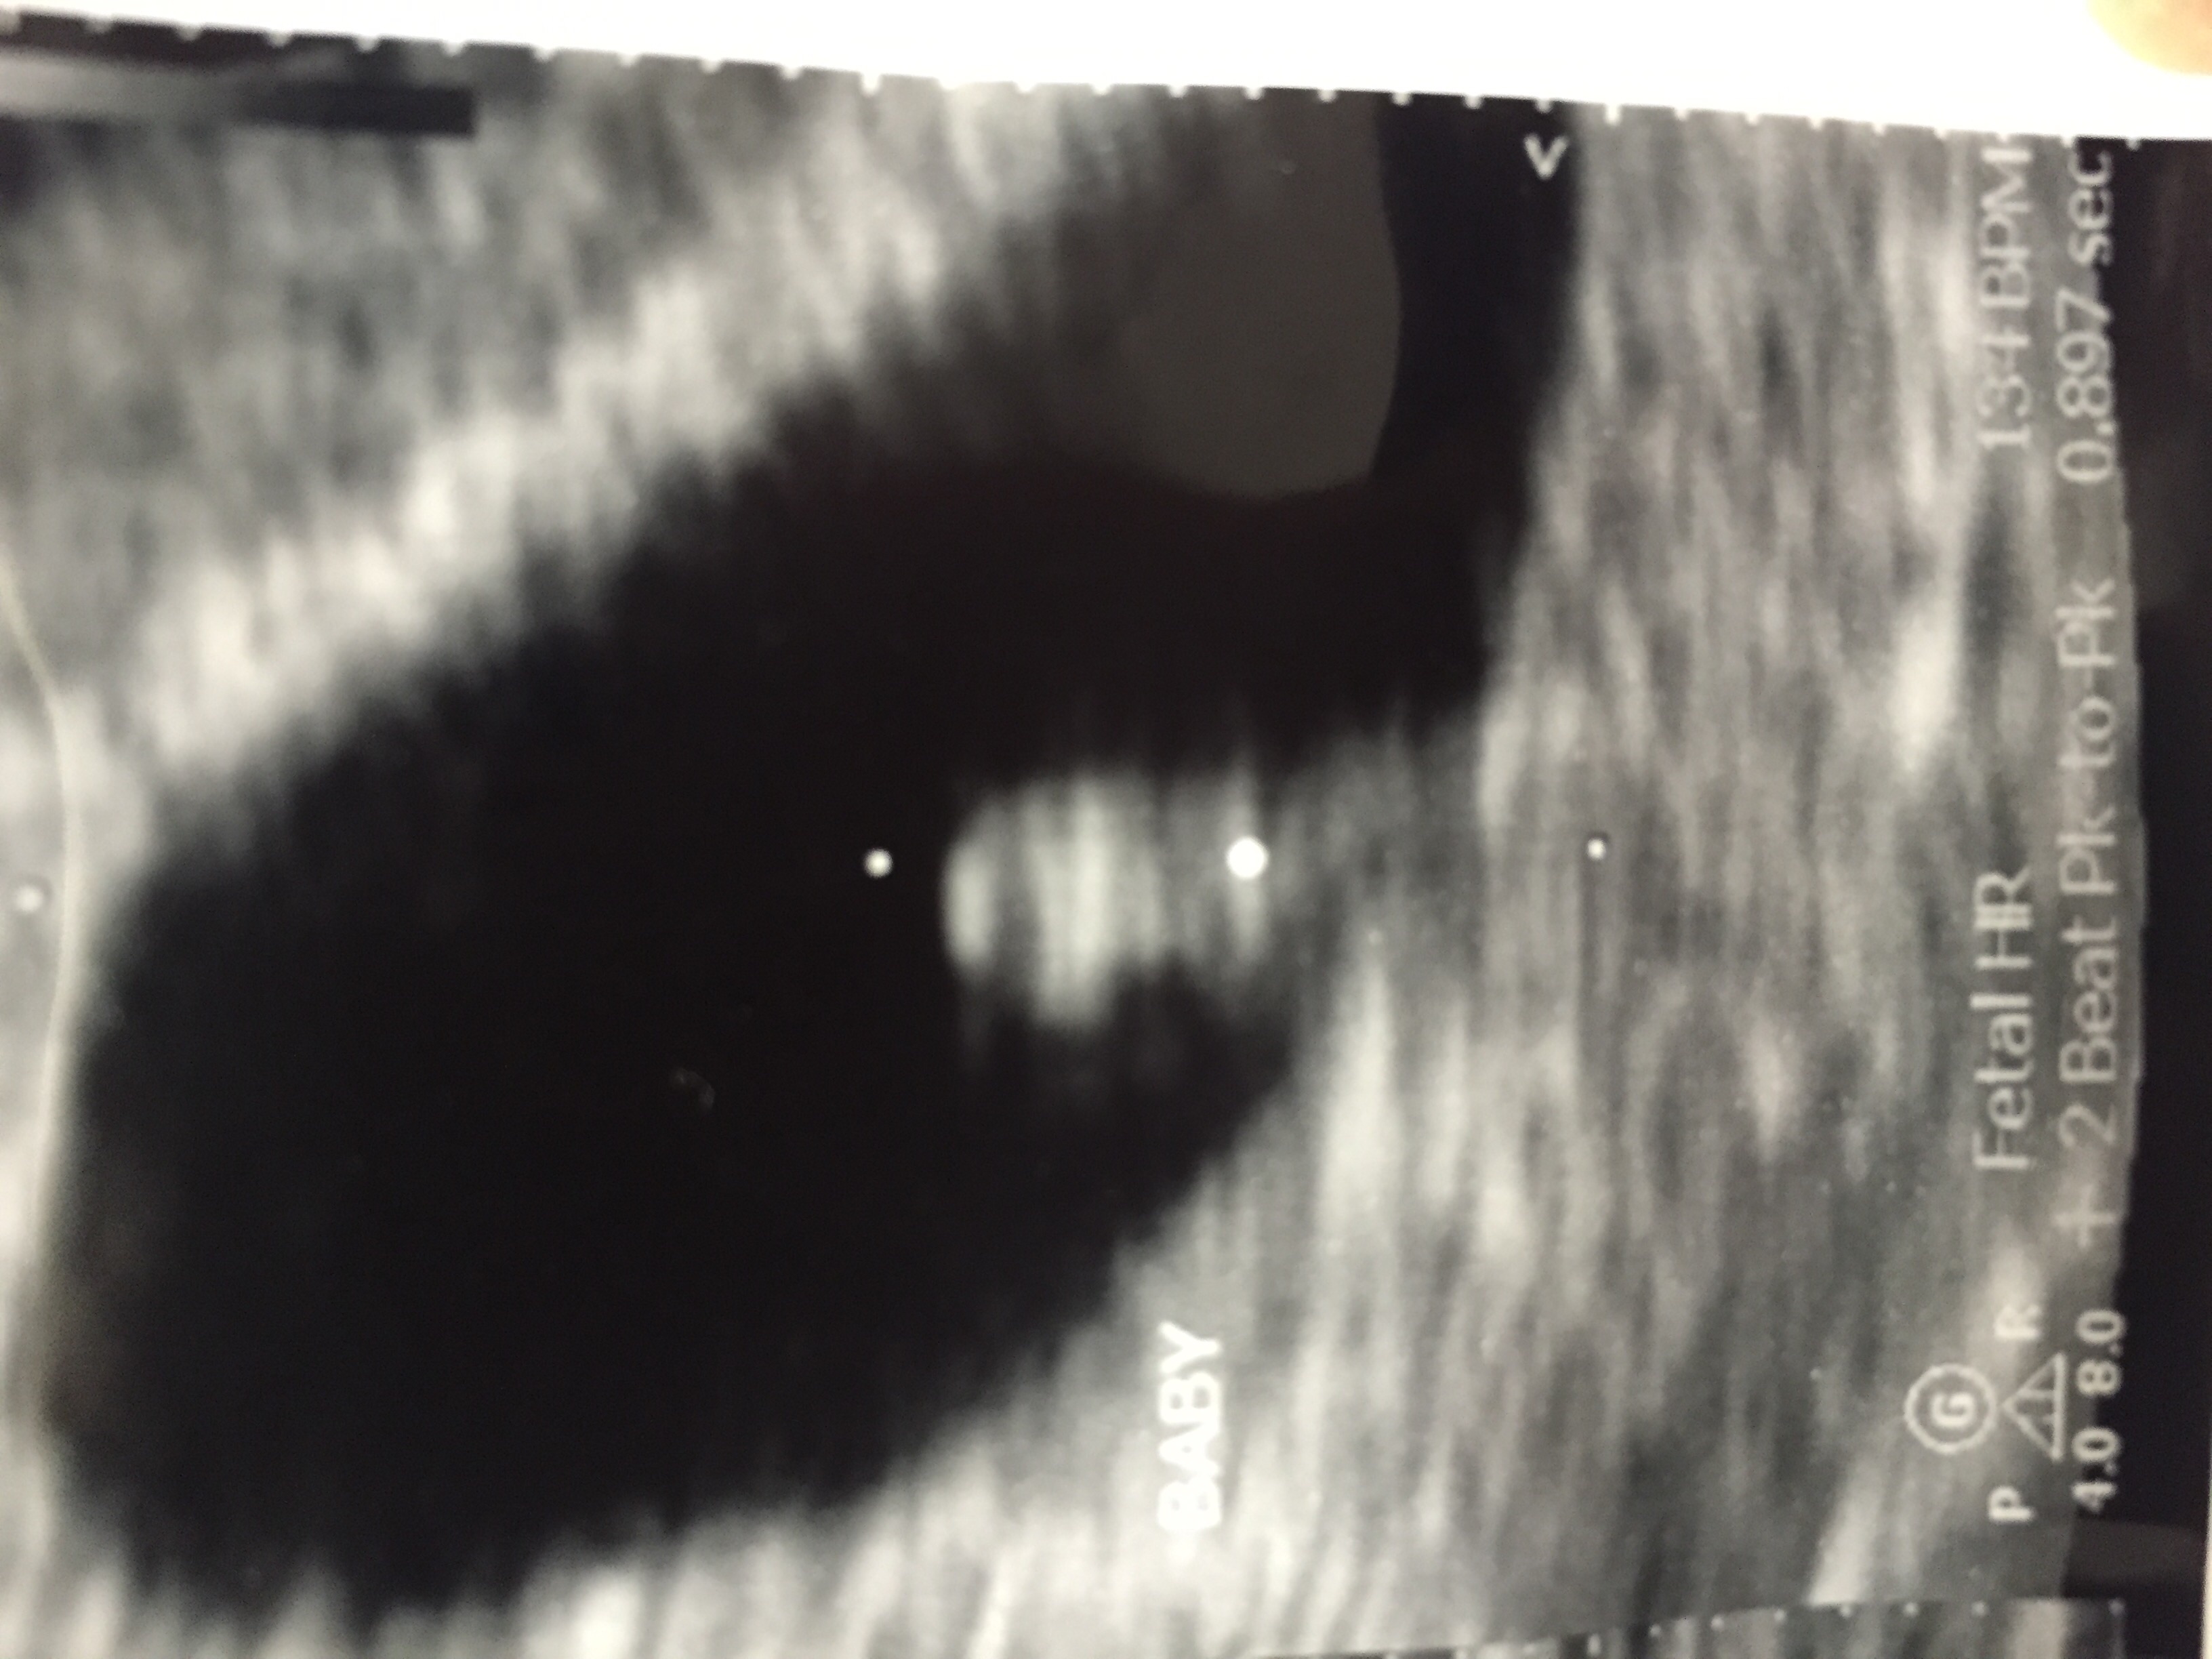

First Sono today and baby is measuring exactly what we thought, 7w3d. Due date 4/15/15. The bottom blob is the baby and the head is on the left with tiny little appendages. Everything looked good, HR 134. So far it's been a good pregnancy, not a lot of symptoms.